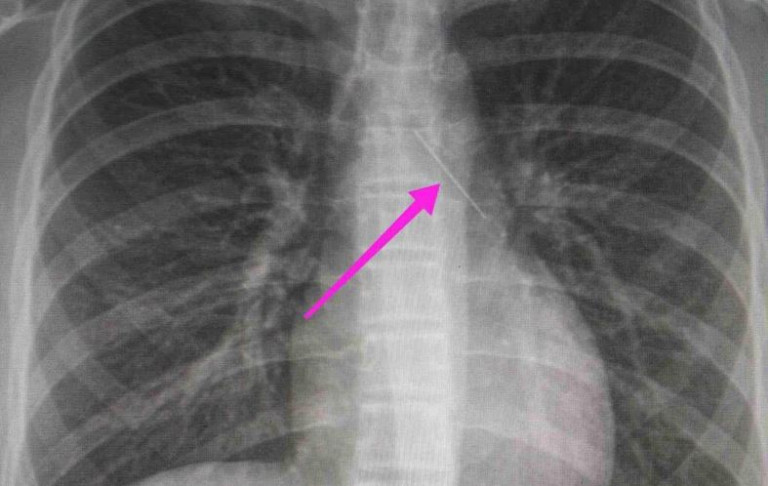

Ανήλικη κατάπιε καρφίτσα - Πώς σώθηκε από τους γιατρούς στο Ιπποκράτειο Θεσσαλονίκης

Ένα ανήλικο κορίτσι μεταφέρθηκε από τους γονείς της στο Ιπποκράτειο Νοσοκομείο Θεσσαλονίκης, καθώς είχε καταπιεί καρφίτσα - Το παιδί έσωσαν οι γιατροί του νοσοκομείου.